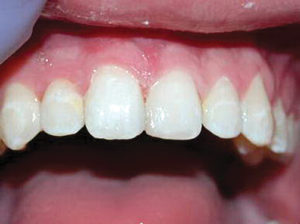

Caso 4

Este adolescente de 16 años tuvo una recaída post-ortodoncia de un diastema de la línea media y era consciente del espacio. Se dieron opciones para cerrar el espacio, incluyendo seis meses de corrección de ortodoncia versus corrección restaurativa con restauraciones directas. Debido a la forma larga y delgada de sus incisivos centrales, el paciente, su madre y yo acordamos que la mejor opción sería la corrección restauradora.

Figura 1. Foto preoperatoria de un diastema de 2.75 mm en un adolescente preocupado (recaída post ortodóntica). |

Figura 2. Después de la colocación de dos matrices Bioclear, los dientes se biselaron ligeramente, se grabaron con ácido y se unieron con Scotchbond Universal. Activa Bioactive Restorative A2 fue colocado y curado. Las restauraciones de los dientes fueron terminadas y pulidas. |

Figura 3. Cuando uso Activa, se notó una naturaleza de mezcla y camaleón del material. Por lo general, combina maravillosamente con el esmalte cuando se coloca como una restauración de un tono en la parte anterior. Se colocó un retenedor fijo 1-1 después de las restauraciones para evitar recaídas adicionales. |